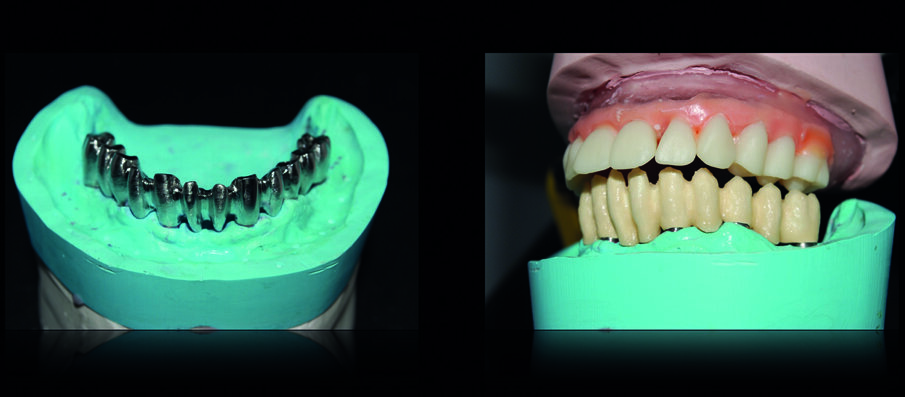

I nuovi modelli master sono stati montati in articolatore in accordo alle procedure di cross-mounting al fine di replicare dimensione verticale, rapporti sagittali tra mascella e mandibola, contatti occlusali, ingombro delle protesi e parametri estetici (Figg. 12, 13). La struttura della protesi inferiore è stata progettata al CAD ed è stata realizzata al CAM fresando un blocco in cromo-cobalto che è stata poi ceramizzata (Figg. 14-16).

La personalizzazione della protesi superiore ha previsto l’utilizzo di denti in disilicato di litio per la sua realizzazione: questo accorgimento ha permesso una durevole stabilità occlusale in assenza di usura degli elementi dentali artificiali della protesi rimovibile (Figg. 17-19).